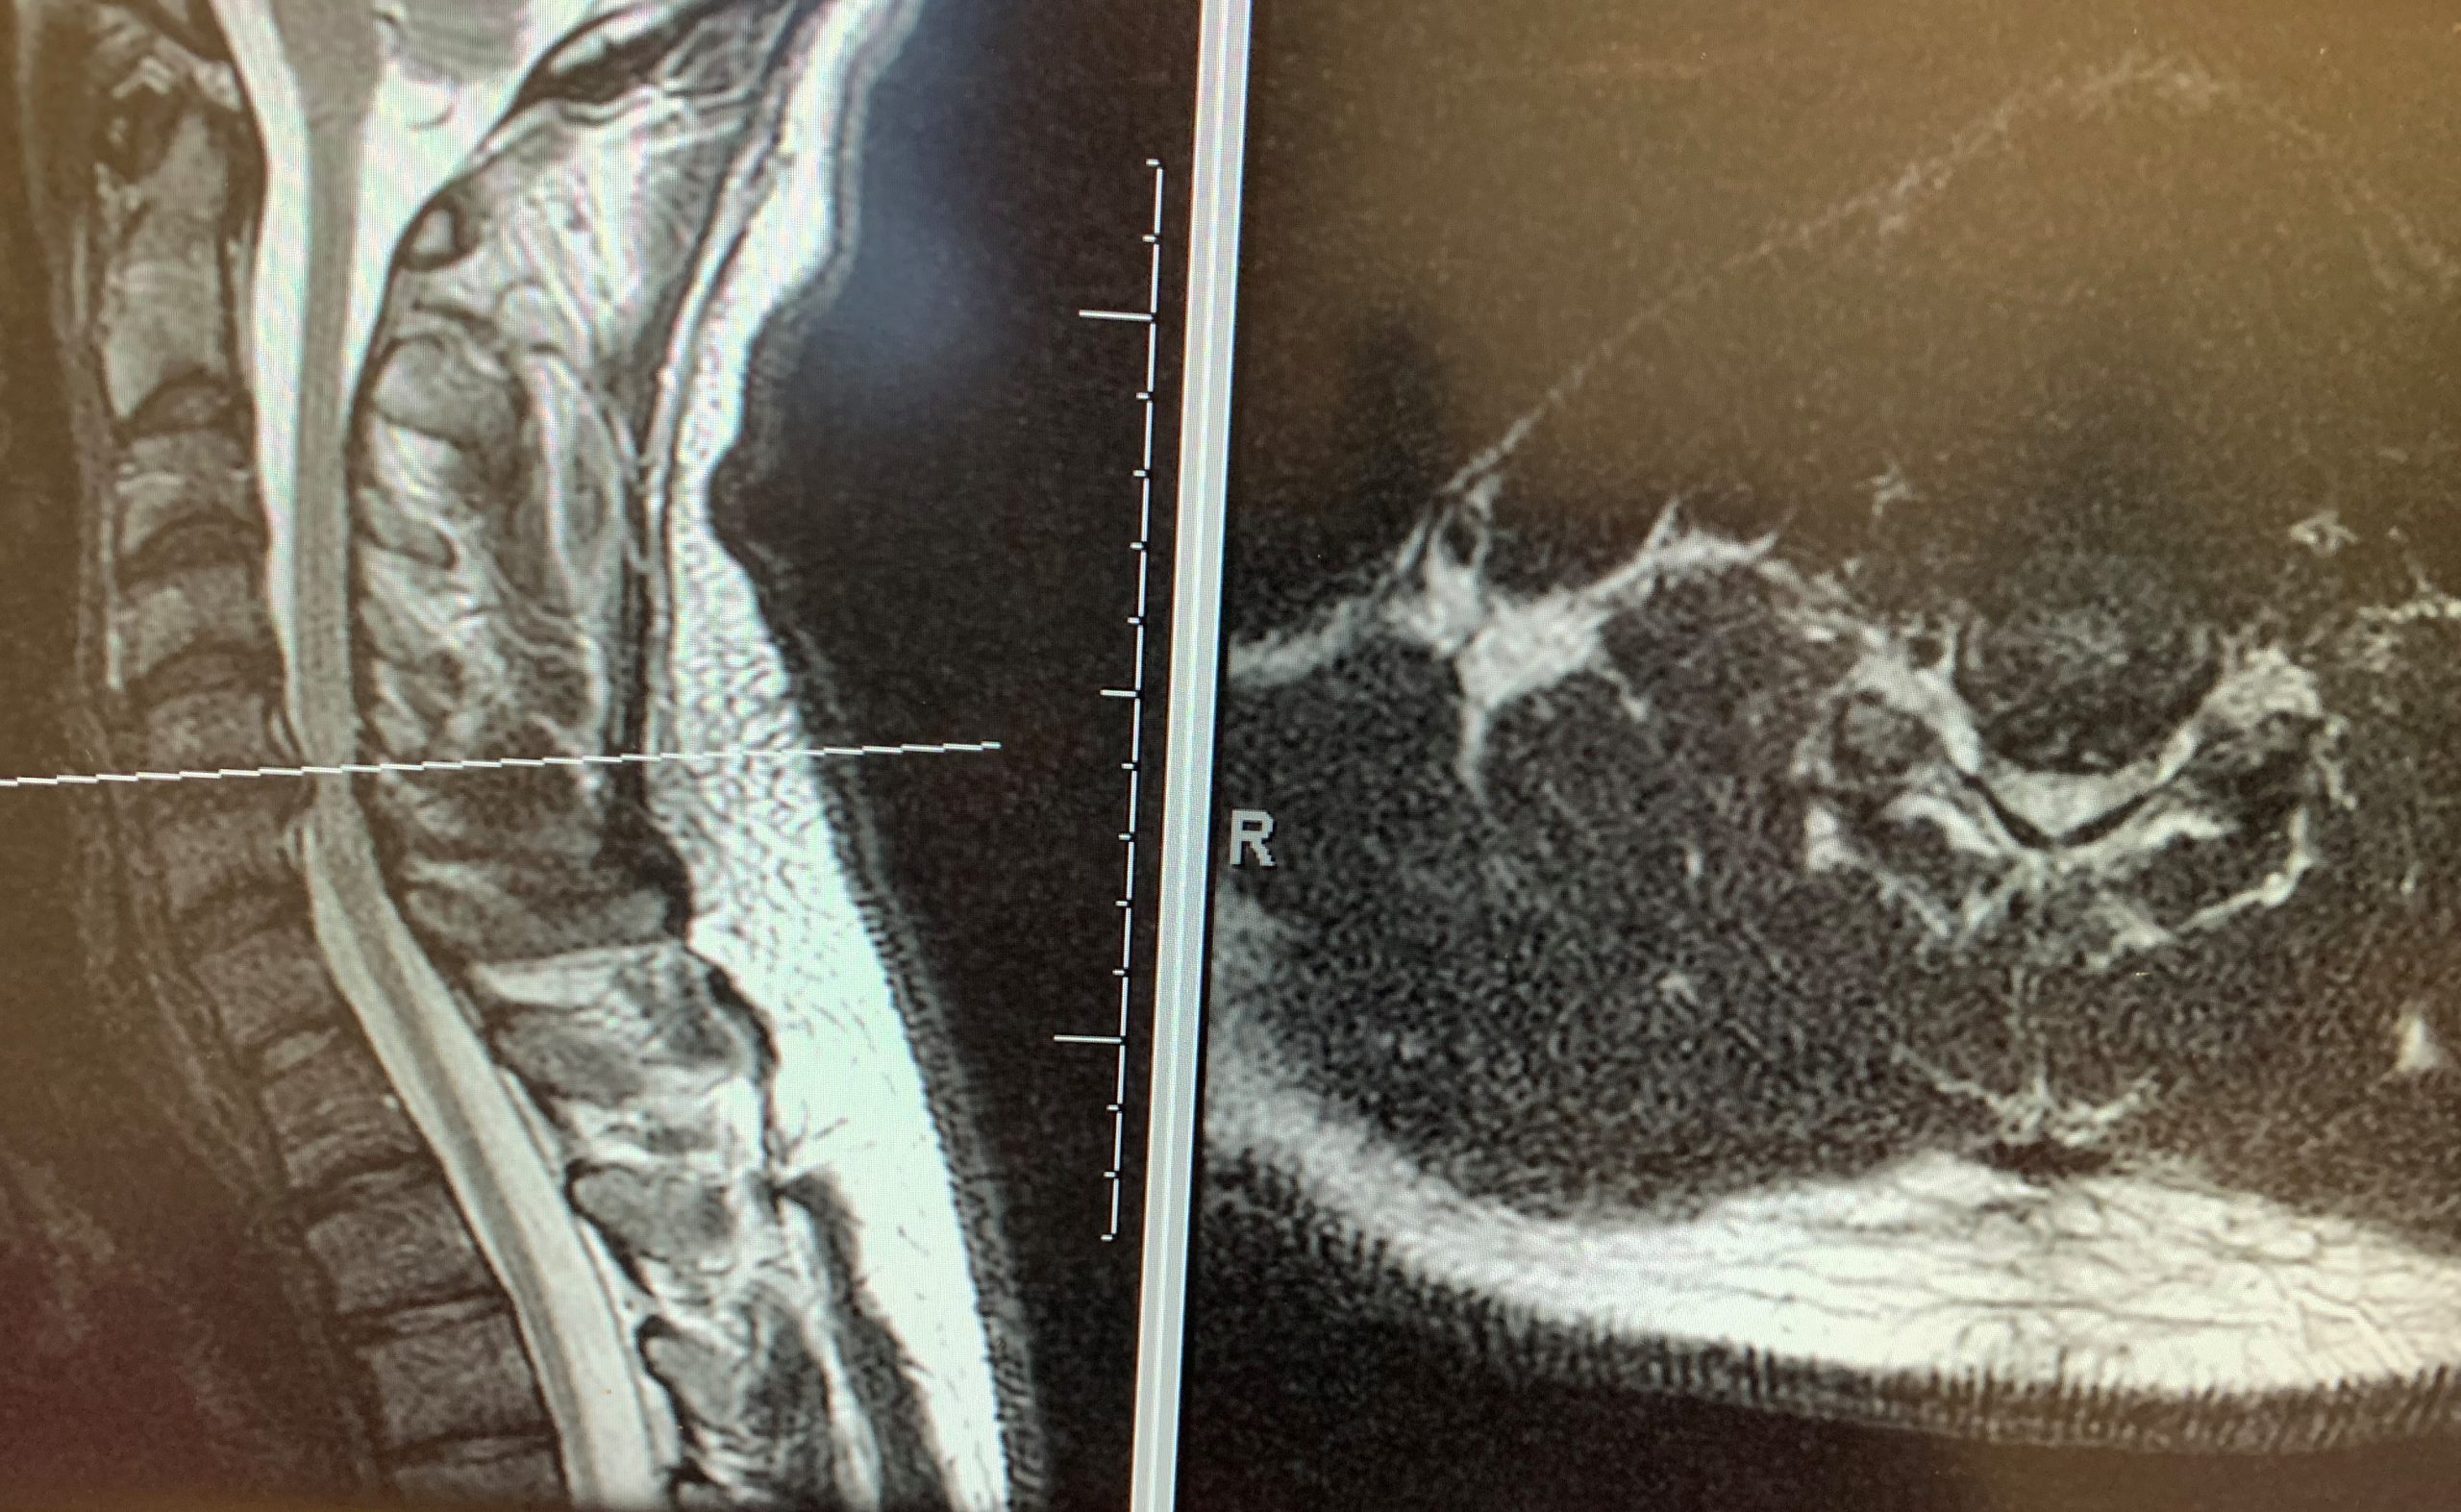

Pre-op MRI with C5/6 disc herniation, subsequent canal compression, and evidence of spinal cord injury.

Patient underwent C5/6 Artificial Disc Replacement and was discharged the next morning.